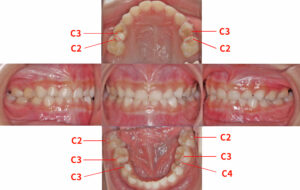

【虫歯の進行レベル】

C0(初期むし歯)

白く濁ったり、ざらついたりする状態。まだ穴はあいておらず、適切なケアで治る可能性あり。

C1(エナメル質のむし歯)

歯の表面に小さな黒ずみが見える。痛みはないことが多い。削って詰める処置が必要。

C2(象牙質のむし歯)

虫歯が内部に進行し、冷たいものがしみる。進行が早いため早めの治療が必要。

C3(神経まで達したむし歯)

ズキズキとした痛みが出る。神経の治療(根管治療)が必要。

C4(歯根まで達したむし歯)

歯の大部分が崩壊し、痛みがなくなることもあるが重度。抜歯になることも。